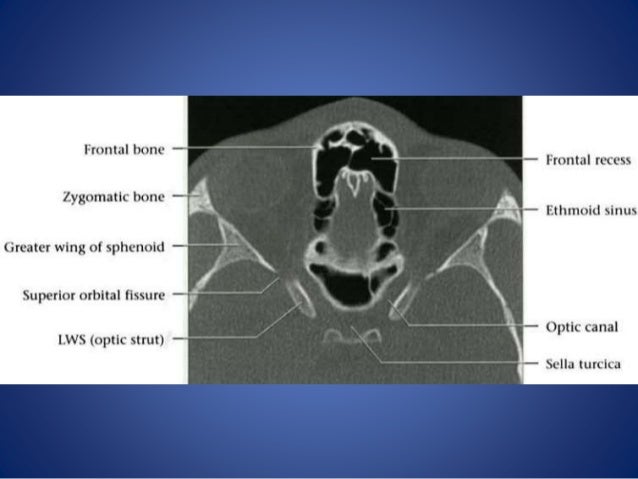

Orbit Imaging Anatomy

Orbit imaging anatomy www.slideshare.net

orbit axial

projection orbital